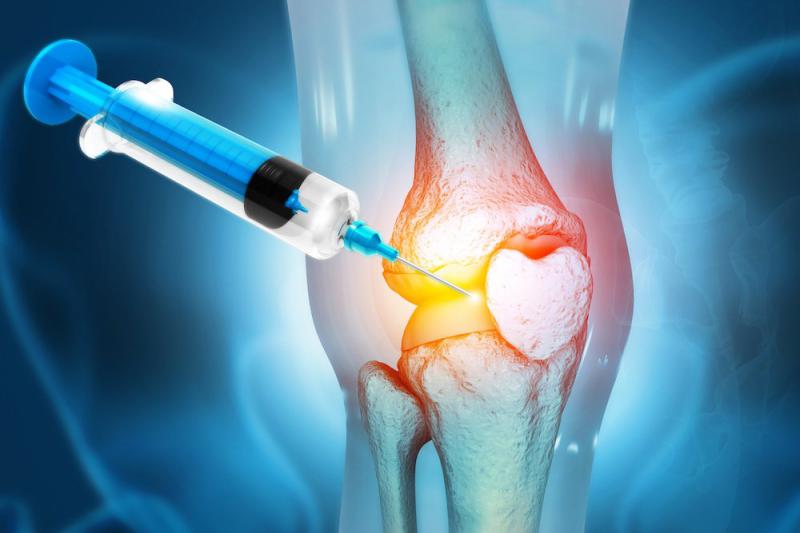

Diz protez ameliyatı, diz eklemi hastalıkları ve yaralanmaları sonucunda oluşan ağrı, hareket kısıtlığı ve yaşam kalitesinin düşmesi gibi sorunları çözmek amacıyla uygulanan cerrahi bir müdahaledir. Ancak, bu tür bir ameliyatın potansiyel riskleri ve sonrası yaşanan durumlar hakkında bilgi sahibi olmak, hastaların bilinçli bir karar vermelerine yardımcı olabilir. Aşağıda, diz protez ameliyatının riskleri ve ameliyat sonrası süreç hakkında detaylı bilgiler sunulmaktadır. Diz Protez Ameliyatının Riskleri Diz protez ameliyatı, her cerrahi işlemde olduğu gibi bazı riskler taşımaktadır. Bu riskler, kişisel sağlık durumu, yaş ve diğer faktörlere göre değişiklik gösterebilir. Aşağıda bu riskler sıralanmıştır:

Ekstra Bilgiler Diz protez ameliyatı, genellikle osteoartrit, romatoid artrit, diz yaralanmaları veya diğer diz hastalıkları nedeniyle uygulanmaktadır. Ameliyat öncesinde, hastalar doktorlarıyla ayrıntılı bir değerlendirme yapmalı ve ameliyatın gerekliliği konusunda bilgilendirilmelidir. Ayrıca, hastaların ameliyat sonrası süreçte kendilerini nasıl hazırlayacakları ve rehabilitasyon programına nasıl uyacakları konusunda bilgi almaları önemlidir. Diz protez ameliyatı, birçok hasta için yaşam kalitesini artıran etkili bir tedavi seçeneği olabilmektedir. Ancak, bu süreçle ilgili risklerin ve ameliyat sonrası gerekliliklerin bilinmesi, hastaların daha iyi bir deneyim yaşamalarına yardımcı olabilir. Bu nedenle, hastaların ameliyat öncesinde ve sonrasında sağlık profesyonelleriyle düzenli iletişimde olmaları teşvik edilmelidir. |